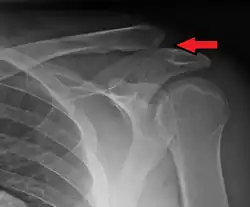

| An Xray showing a separated shoulder. Notice the separation between the end of the collarbone and the scapula. | |

X-ray indicates a separated shoulder when the acromioclavicular joint space is widened (it is normally 5 to 8 mm).[9]